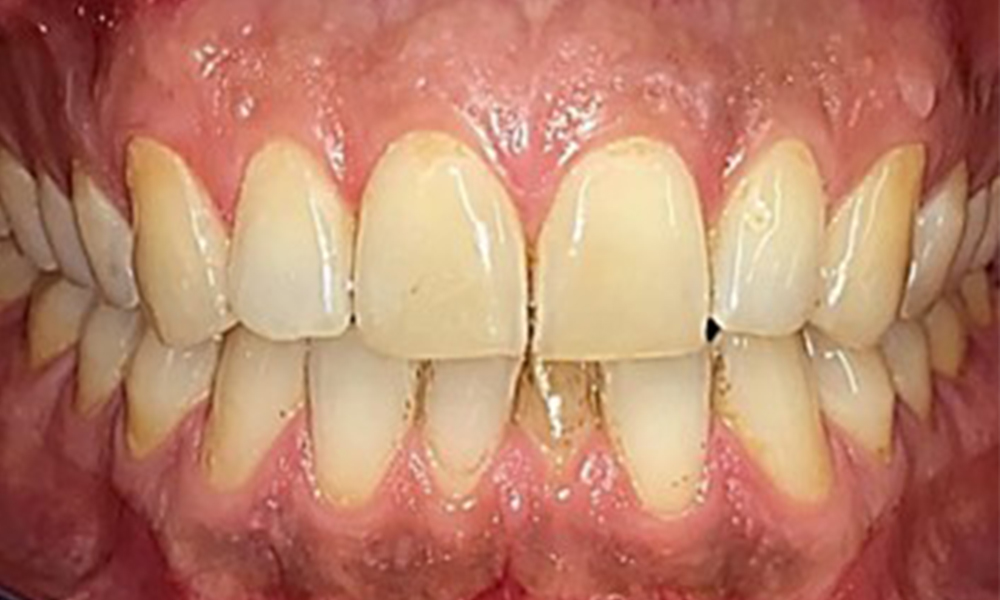

Няма патологични екстраорални резултати. По време на интраоралния преглед се установи кафеникаво оцветяване в близост до кератинизираната гингива и при прехода към подвижната лигавица (фиг. 2), което може да се отдаде на консумацията на никотин. В областта на небцето, особено в близост до небцовите повърхности на максиларните молари, се наблюдават белезникави лезии на лигавицата, които показват повишена кератинизация и също могат да се припишат на консумацията на никотин. Езикът е покрит с бяло-кафеникаво покритие, което може да се отстрани.

Пациентът има пълно съзъбие с общо 28 зъба. Налице са забележими ерозии и атриции. (Фиг. 4, Фиг. 5). Поради бруксизъм пациентът е носил шина с коригиран блок на захапката през нощта в продължение на много години. Ерозиите са причинени от продължителна консумация на изотонични напитки. Не сe наблюдава загуба на пародонтална кост или активни кариозни лезии.